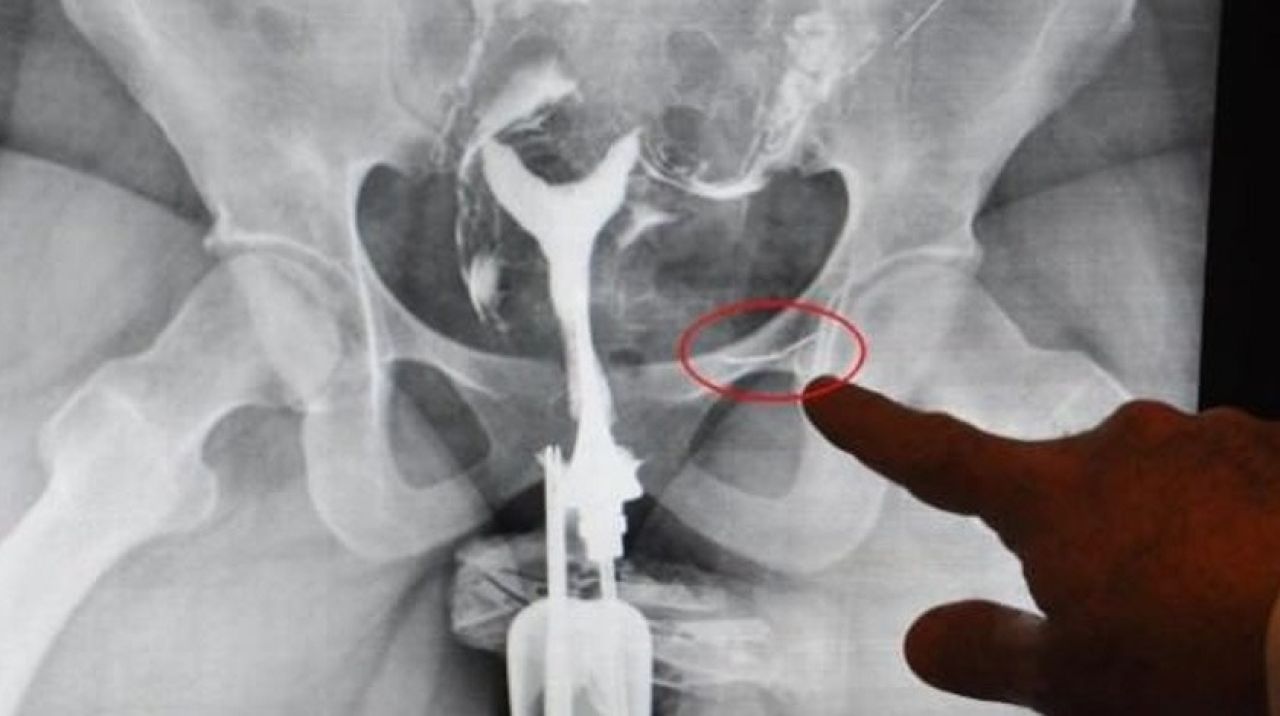

S.Ş. adlı Azeri kadın, yakın zamanda tanıştığı eşiyle dünyaevine girip, Denizli'ye yerleşti. Yıllar geçmesine rağmen çocuk sahibi olamayan S.Ş., eşiyle birlikte tedavi için Denizli Özel Sağlık Hastanesi'ne başvurdu. Başhekim olan Kadın Hastalıkları ve Doğum Uzmanı Opr. Dr. Rıdvan Erdemir ile görüşen S.Ş.'nin, çekilen röntgen filminde, rahim kanallarının tıkalı olduğu tespit edildi. Ayrıca filmde, mesane bölgesinde yabancı cisim görüldü. Ameliyata alınan S.Ş.'nin çocuk sahibi olabilmesi için tedavisi yapılırken, mesane torbası dışına yapışmış görülen yabancı cismin de dikiş iğnesi olduğu belirlendi. Dikiş iğnesi, ameliyatla çıkarıldı.

Operasyon hakkında bilgi veren Opr. Dr. Rıdvan Erdemir ise "Hastamız geldiğinde bize iğneden bahsetmedi. Çocuk tedavisi için çektiğimiz filmde, orada olmaması gereken yabancı bir cisim gördük. Ameliyatta çıkardığımızda cismin dikiş iğnesini olduğunu görünce şaşırdık. 16 yıl bu iğneyle yaşamış. İğne mideden bağırsaklara geçmiş, bağırsakları deldikten sonra mesane torbasının dışına yapışmış ve yağ bağlamış. İğne adeta karın boşluğunda dolaşmış. Önemli olan hayati organlara zarar vermemesi" diye konuştu.